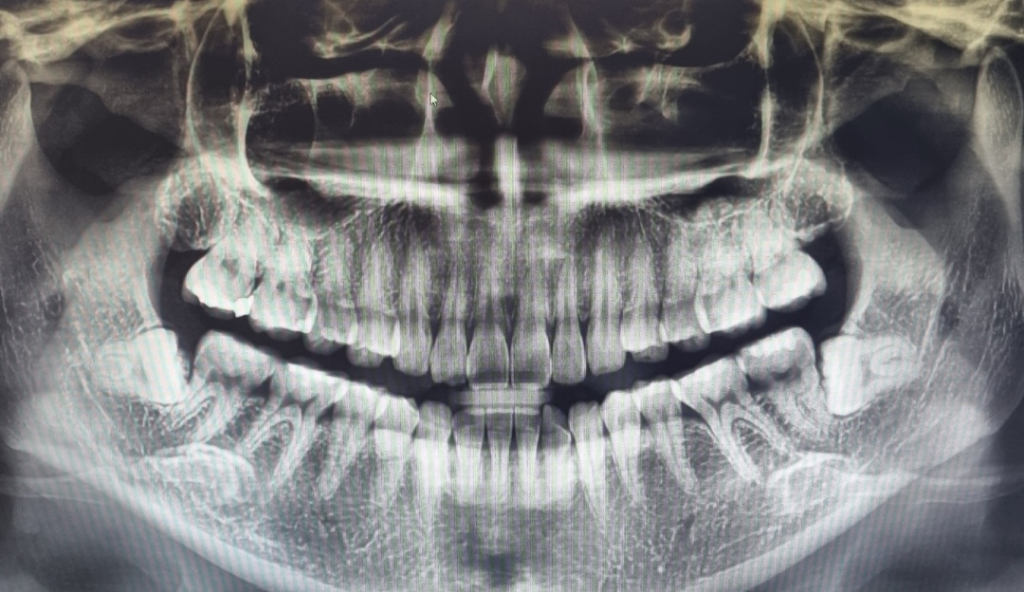

치아마모가 심한편인가요? 관리를 어떻게 해야할까요?

1. 치아 마모가 심각한 수준일까요?

• 2번 째 사진

사진상으로 보면 치아 마모상태가 심한거 같진 않습니다. 턱관절이 아프거나 그럴경우에는 스플린트나 보톡스 치료를 받으시면될것같습니다.

1. 사진상 치아 마모가 아주 심한 수준은 아니라고 판단됩니다.